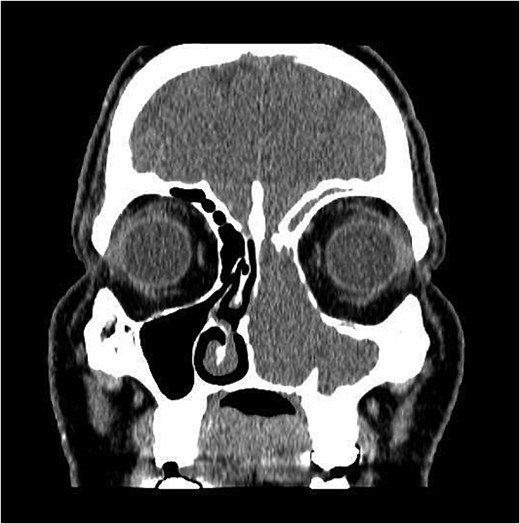

CT showed a heterogeneously enhancing mass completely occluding the left nasal cavity, left ethmoidal, maxillary and frontal sinuses, extending to left pterygopalatine fossa. It is associated with bony erosion of the posterior nasal septum and the left medial maxillary wall (Figs 1 and 2). Findings were suggestive of inverted papilloma vs sinonasal malignancy. Therefore, biopsy was recommended.

Coronal section of CT paranasal sinus with contrast bone window showing the bony erosion in the nasal septum and maxillary sinus wall.